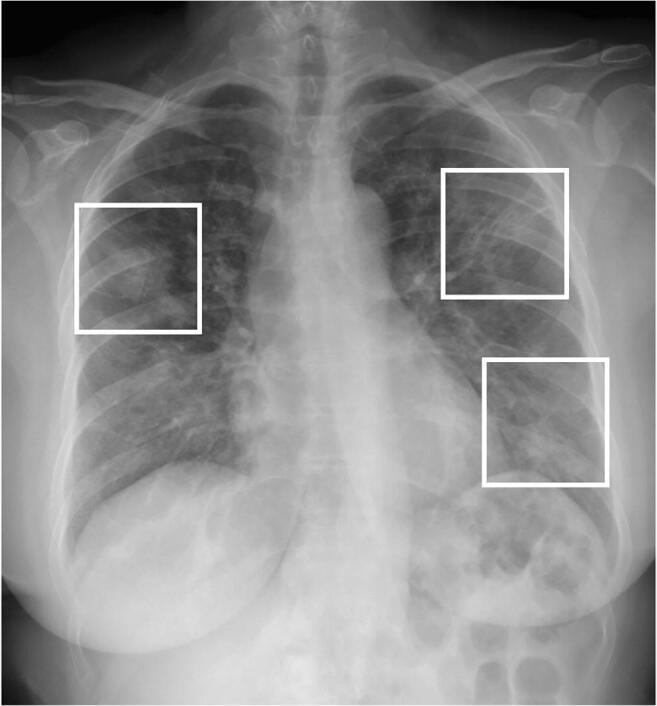

COVID-19 has infected more than 2 million people in the world in less than 5 months outbreak. Chest imaging is recommended for triage of suspected cases of COVID-19 with moderate-severe clinical features and high pre-test probability of disease, and may help for patient follow-up and to identify patients at higher risk of disease worsening. This pictorial essay illustrates typical and uncommon imaging findings of COVID-19 pneumonia and the role of imaging for patient management.

在不到5个月的爆发期内,新冠病毒肺炎已在全球感染了超过200万人。对于具有中重度临床特征且疾病预检概率高的新冠病毒肺炎疑似病例,建议进行胸部成像检查,这可能有助于患者的随访,并识别疾病恶化风险较高的患者。这篇图文并茂的文章阐述了新冠病毒肺炎的典型和不常见的影像学表现以及成像在患者管理中的作用。